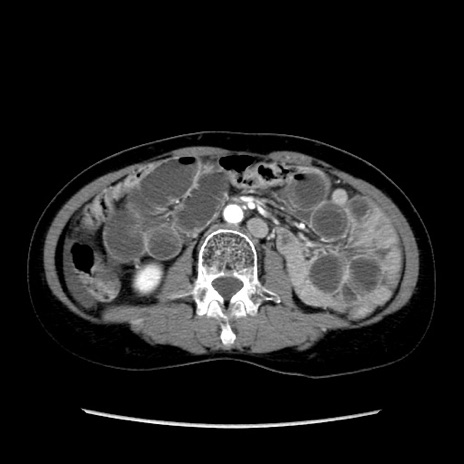

症例32(横断像)

【症例】40歳代 女性

【主訴】上腹部痛、嘔気・嘔吐

【現病歴】約9時間前頃から急に上腹部痛、嘔気、嘔吐が出現。改善しないため救急要請。

【既往歴】子宮頚癌(広汎子宮全摘術、放射線療法)、腸閉塞

【身体所見】腹部:平坦、軟、腸雑音亢進、上腹部を中心に腹部全体に圧痛あり。

【データ】WBC 8400、CRP 0.03